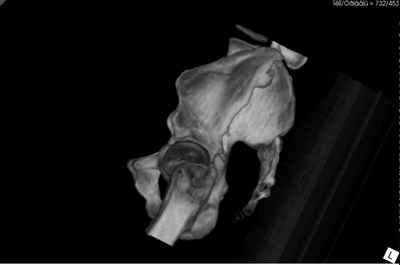

перелом таза 9-ти месячной давности.

Пациенту чуть больше сорока лет, работал в МЧС, после ДТП лечился по месту жительства консервативно. Жалобы пациента на постоянные боли в месте перелома, ощущение подвижности в месте перелома при ходьбе. Передвигается без дополнительной опоры, хромота не щадящая. Клинически отчетливо определяется патологическая подвижность крыла левой подвздошной кости. R-ммы не высылаю, сразу 3-D, если не хватит дошлю снимки.

Андрей, на 3d снимках не видно соотношение суставных поверхностей, величину диастаза в ложном суставе и состояние головки (может уже протез нужен).

Нужны стандартные снимки и срезы на уровне сустава и тела подвздошной кости.